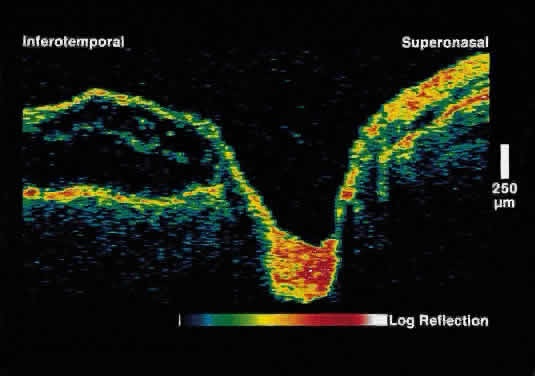

Serous Macular Detachment Secondary to Optic Nerve Pit Optical coherence tomography images of this clinical entity clearly demonstrate

the relation between the optic nerve pit and serous macular detachment (Fig. 4). These images support the concept that fluid from the optic pit directly

enters the neurosensory retina and not the subretinal space.13  Fig. 4. OCT image through macula and optic disc in a patient with an optic nerve

head pit. The optic pit is contiguous with a schisis-like cavity in

the inner retina and not with the subretinal space. Fig. 4. OCT image through macula and optic disc in a patient with an optic nerve

head pit. The optic pit is contiguous with a schisis-like cavity in

the inner retina and not with the subretinal space.